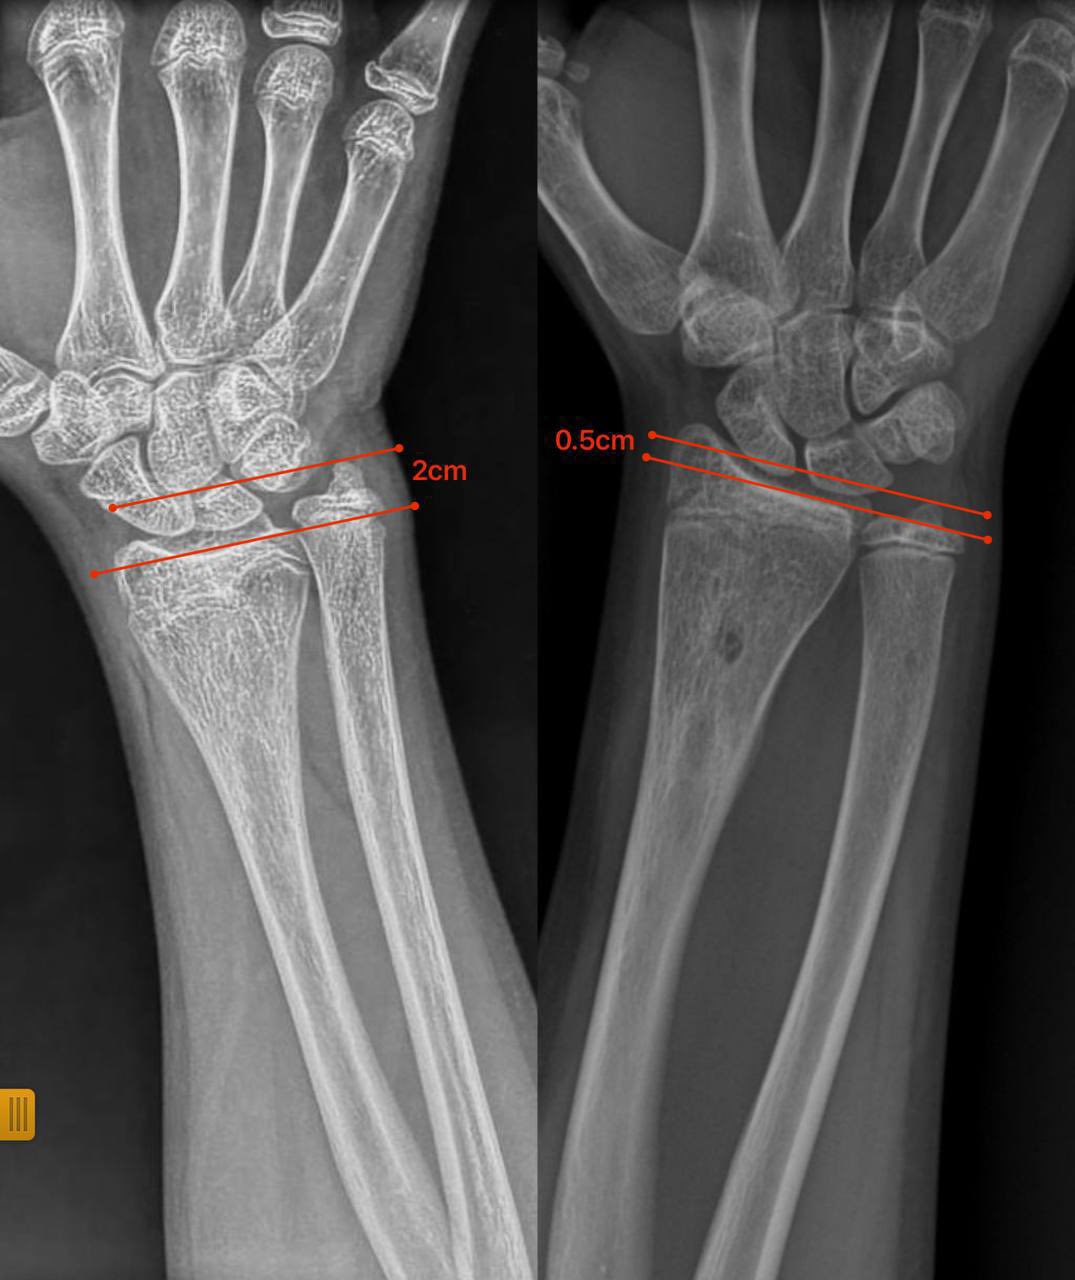

В ортопедо-травматологічному відділенні Закарпатської обласної дитячої лікарні успішно провели малотравматичну операцію 12-річній дівчинці з післятравматичною деформацією передпліччя. Через травму в неї утворився кістковий місток, який заблокував ріст кістки та спричинив її викривлення. Під час втручання лікарі ендоскопічно видалили кістковий місток, без остеотомій та встановлення металоконструкцій. Уже за сім місяців ріст кістки нормалізувався, форма передпліччя відновилася, а рухливість кінцівки збережена.